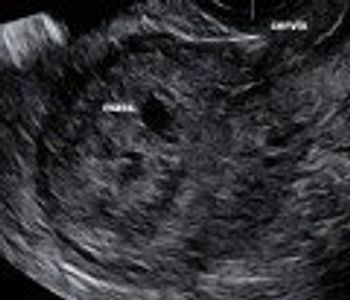

Postabortal placental polyps and uterine arteriovenous malformations can look identical on ultrasonography. Read how saline instillation sonohysterography helped discern the diagnosis.